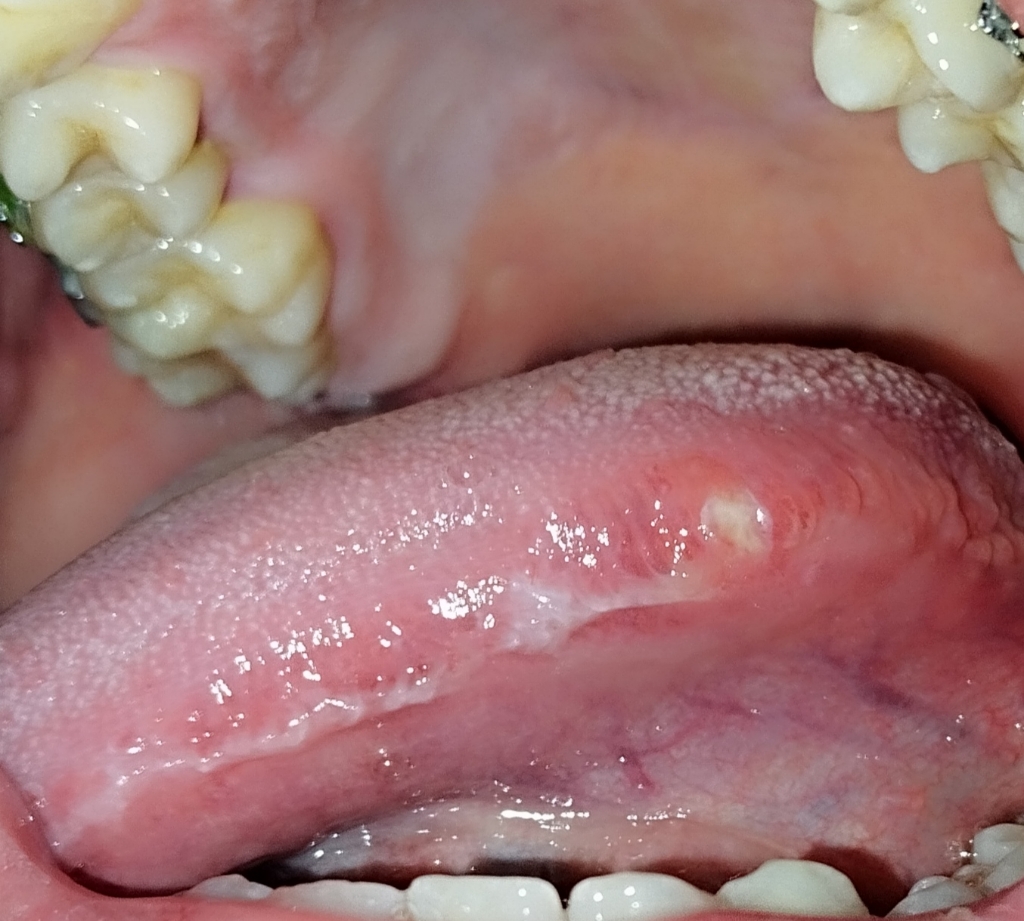

Em chào bác sĩ em là nam 20 tuổi hôm qua em có cảm giác hơi khó chịu ở vùng cạnh lưỡi và đi soi gương phát hiện ra có 1 vết trợt nhỏ màu trắng đến hôm nay bắt đầu đau nhiều và đau lan lên tai, nó gây đau và rất khó khăn khi ăn và nói chuyện, vết trợt này không chảy máu, không có mùi, sờ vào mềm không chai cứng bác sĩ cho em hỏi đấy có phải vết nhiệt ở lưỡi không hay là ung thư lưỡi ạ, và bác sĩ có thể nói cụ thể hơn về ung thư lưỡi không ạ ? Em có cần thiết phải đi sinh thiết không ? Hiện tại em đang rất lo lắng mong bác sĩ trả lời giúp em. Em cảm ơn bác sĩ nhiều